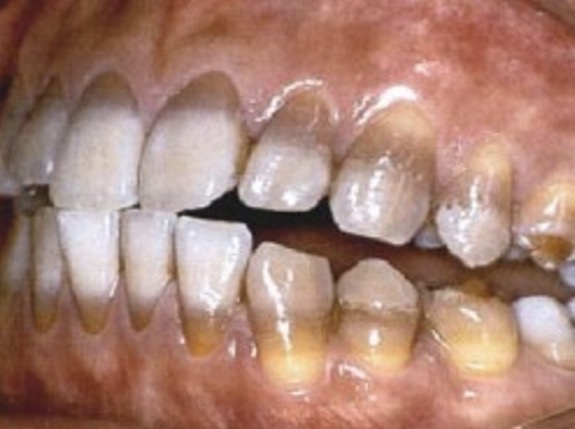

This child's teeth erupted like this. What is the condition?

Hutchinson's incisors from congenital syphilis